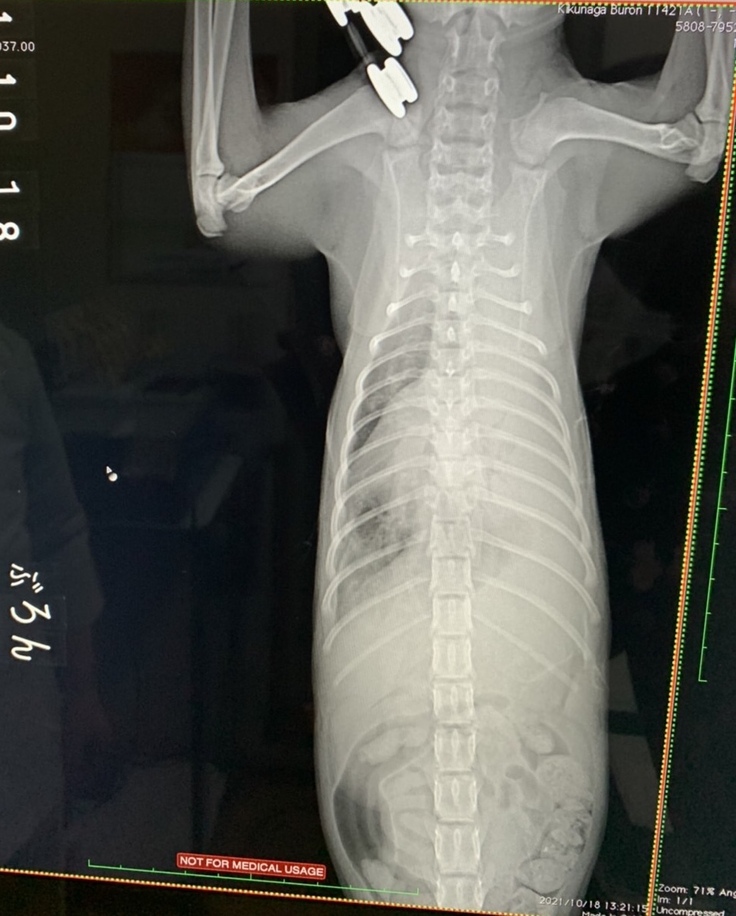

レントゲン検査の結果、左肺が真っ白に写っていました。胸腔内に胸水が溜まっていて、胸水が肺を圧迫していたたため、白くなっているのは酸素が入っていないことを示し、左肺がしぼんで機能していない状態でした(無気肺)。心音もほとんど聞こえない状態でした。この状態が続くと肺が元通りにはふくらまない、もしくは急にふくらんだ場合、毒素が全身に回り危険な状態になるという説明を受けました。

肺のレントゲン

レントゲン検査

無気肺の可能性があるため、肺のレントゲン検査を毎週とることになりました。

わずかですが、白い部分が減ってきています。